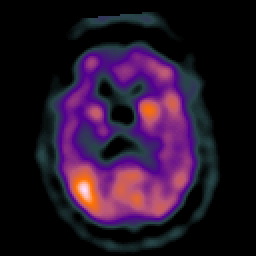

Subacute Stroke overlay -- Slice #14

[Home][Help][Clinical] Slice 14